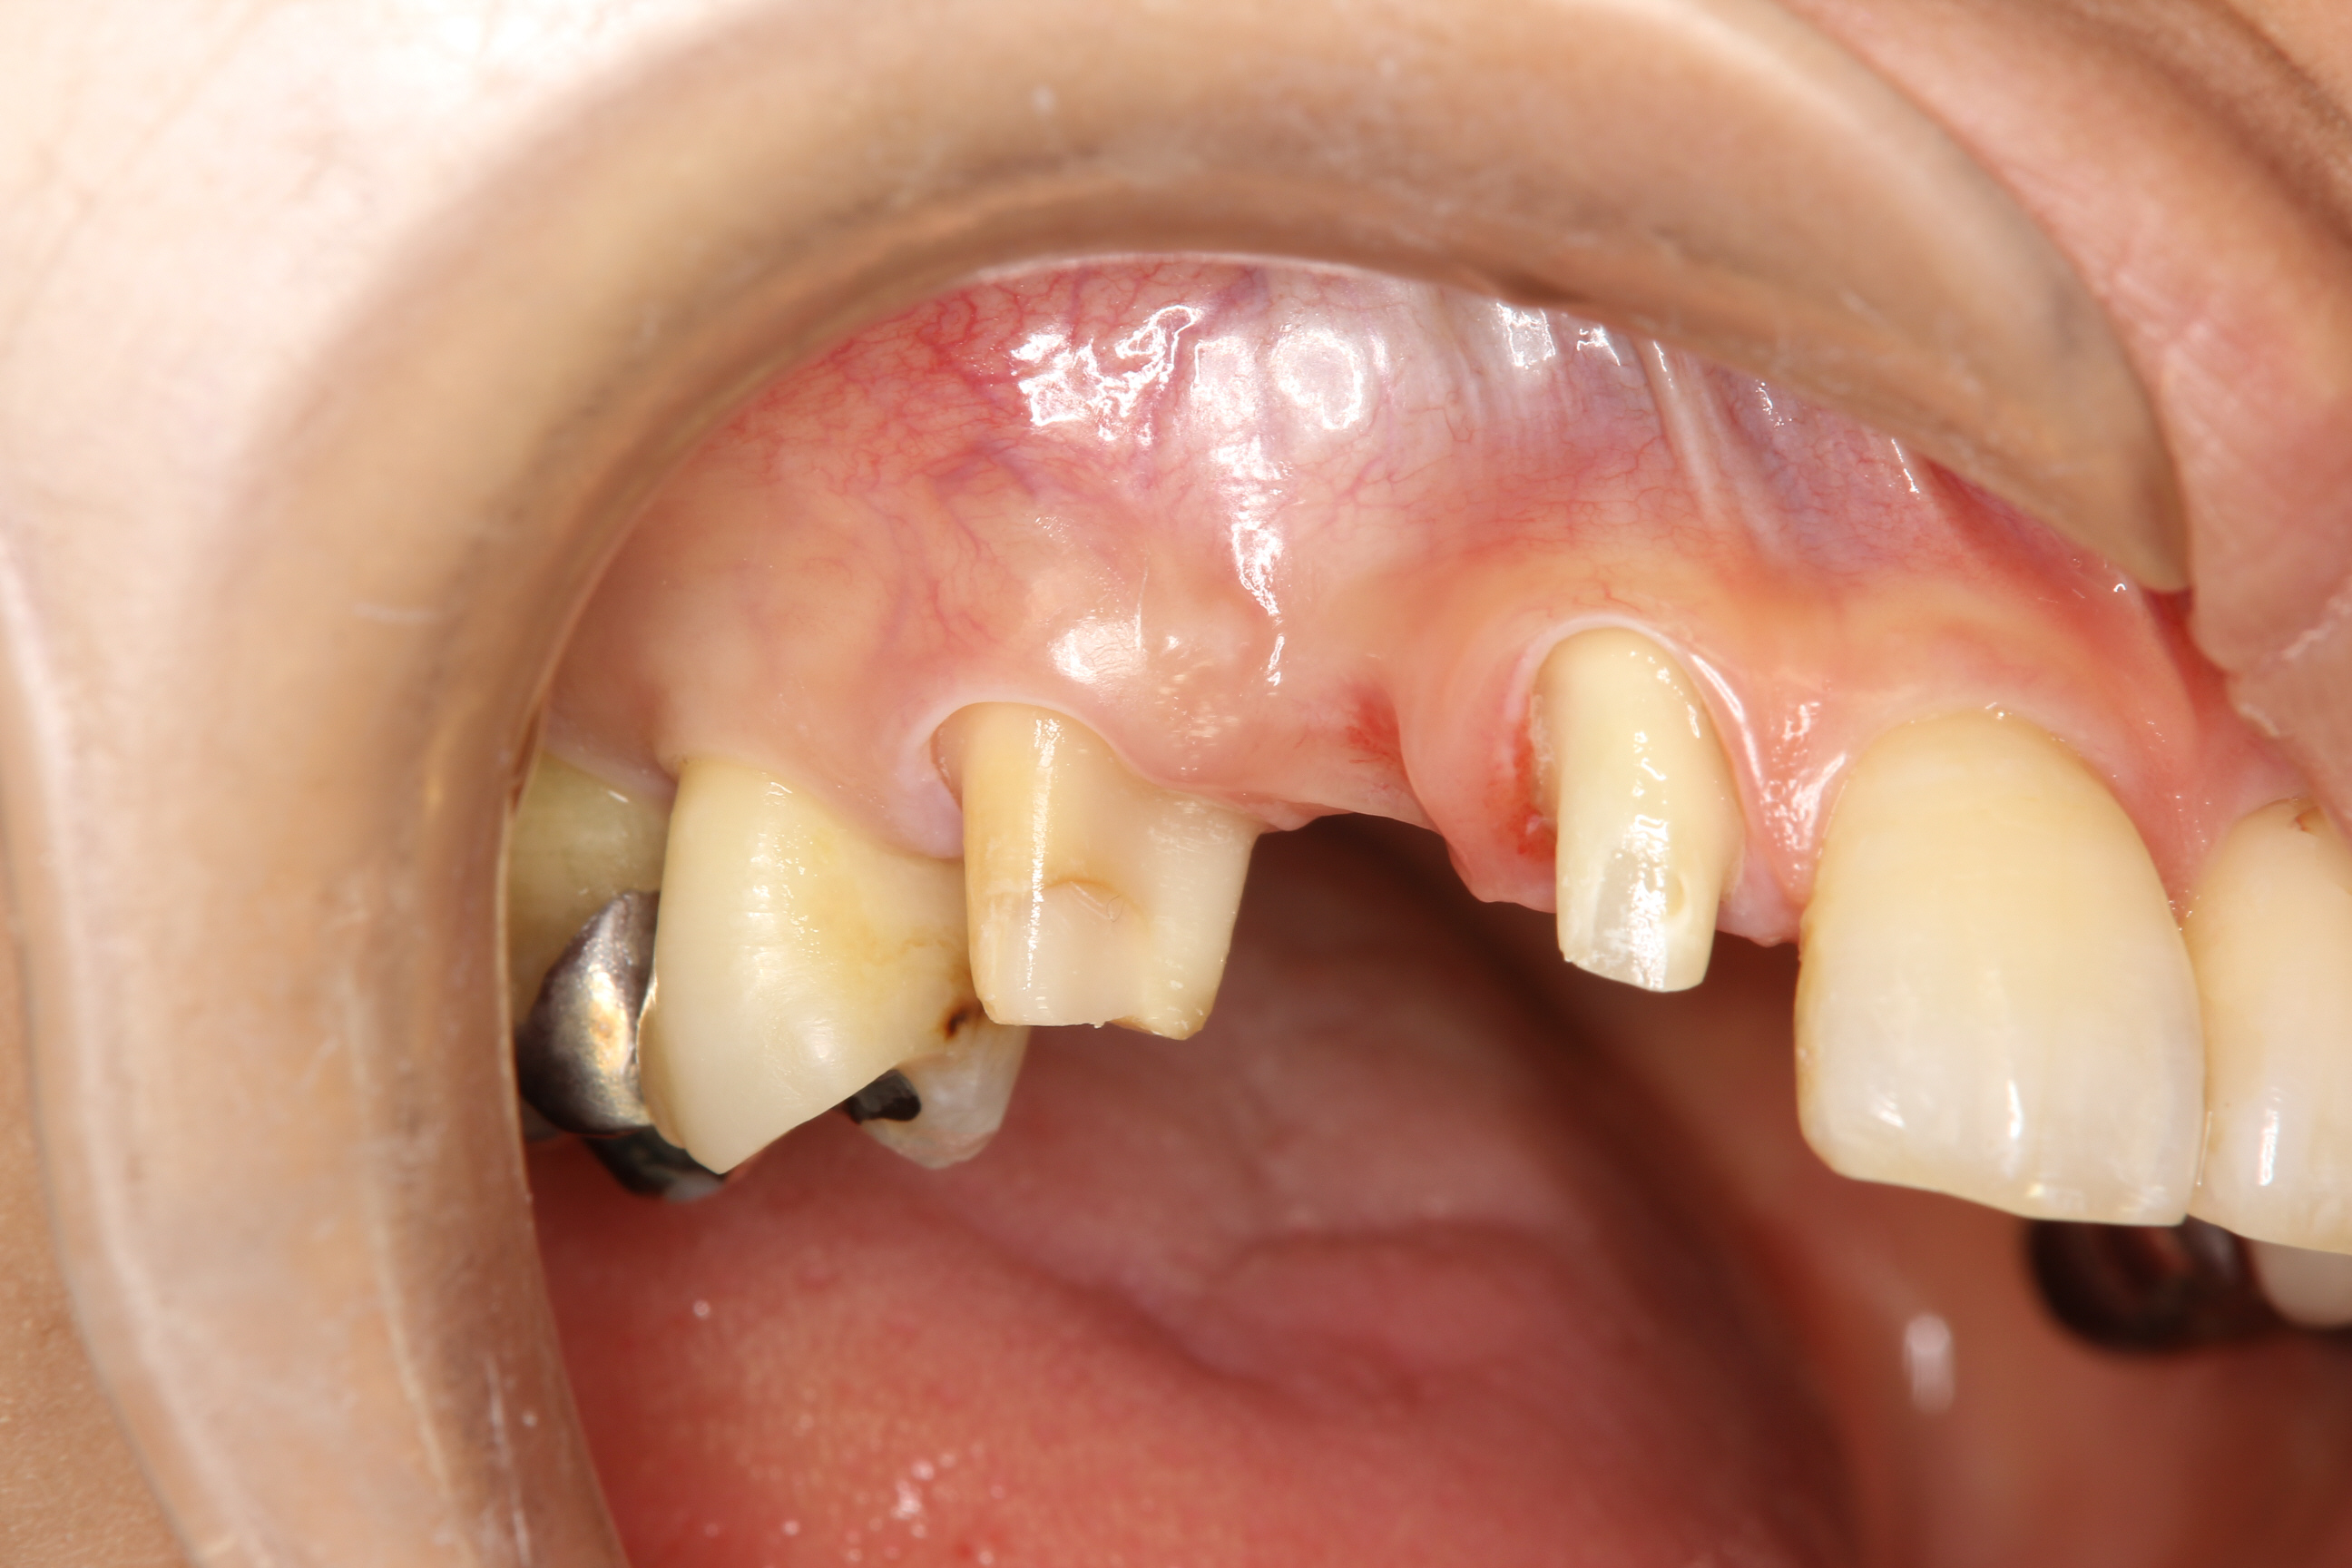

下の写真は、右上の犬歯のクラウンが脱離したとのことで来院された患者さん。

クラウンだけでなく、コアと呼ばれる土台も一緒に脱離していました。

コアごと脱離した際に多いのですが、レントゲン診査を行ったところ、やはり歯根が垂直的に破折してしまっている状態でした。

破折の仕方によっては、破折片を除去して、矯正などにより歯を引き出してクラウンを装着することも可能ですが、今回のように根の先端付近まで垂直的に破折している状態では保存が困難でした。

患者さんに説明・相談し、抜歯を行って欠損部をブリッジで治すことになりました。

抜歯後に、犬歯の奥の歯のクラウンを除去。そして、クラウンを除去した歯と犬歯の手前の歯を支台歯形成し、ブリッジが装着できるようにします。

下の写真は、ブリッジを作製する準備が終わった状態です。